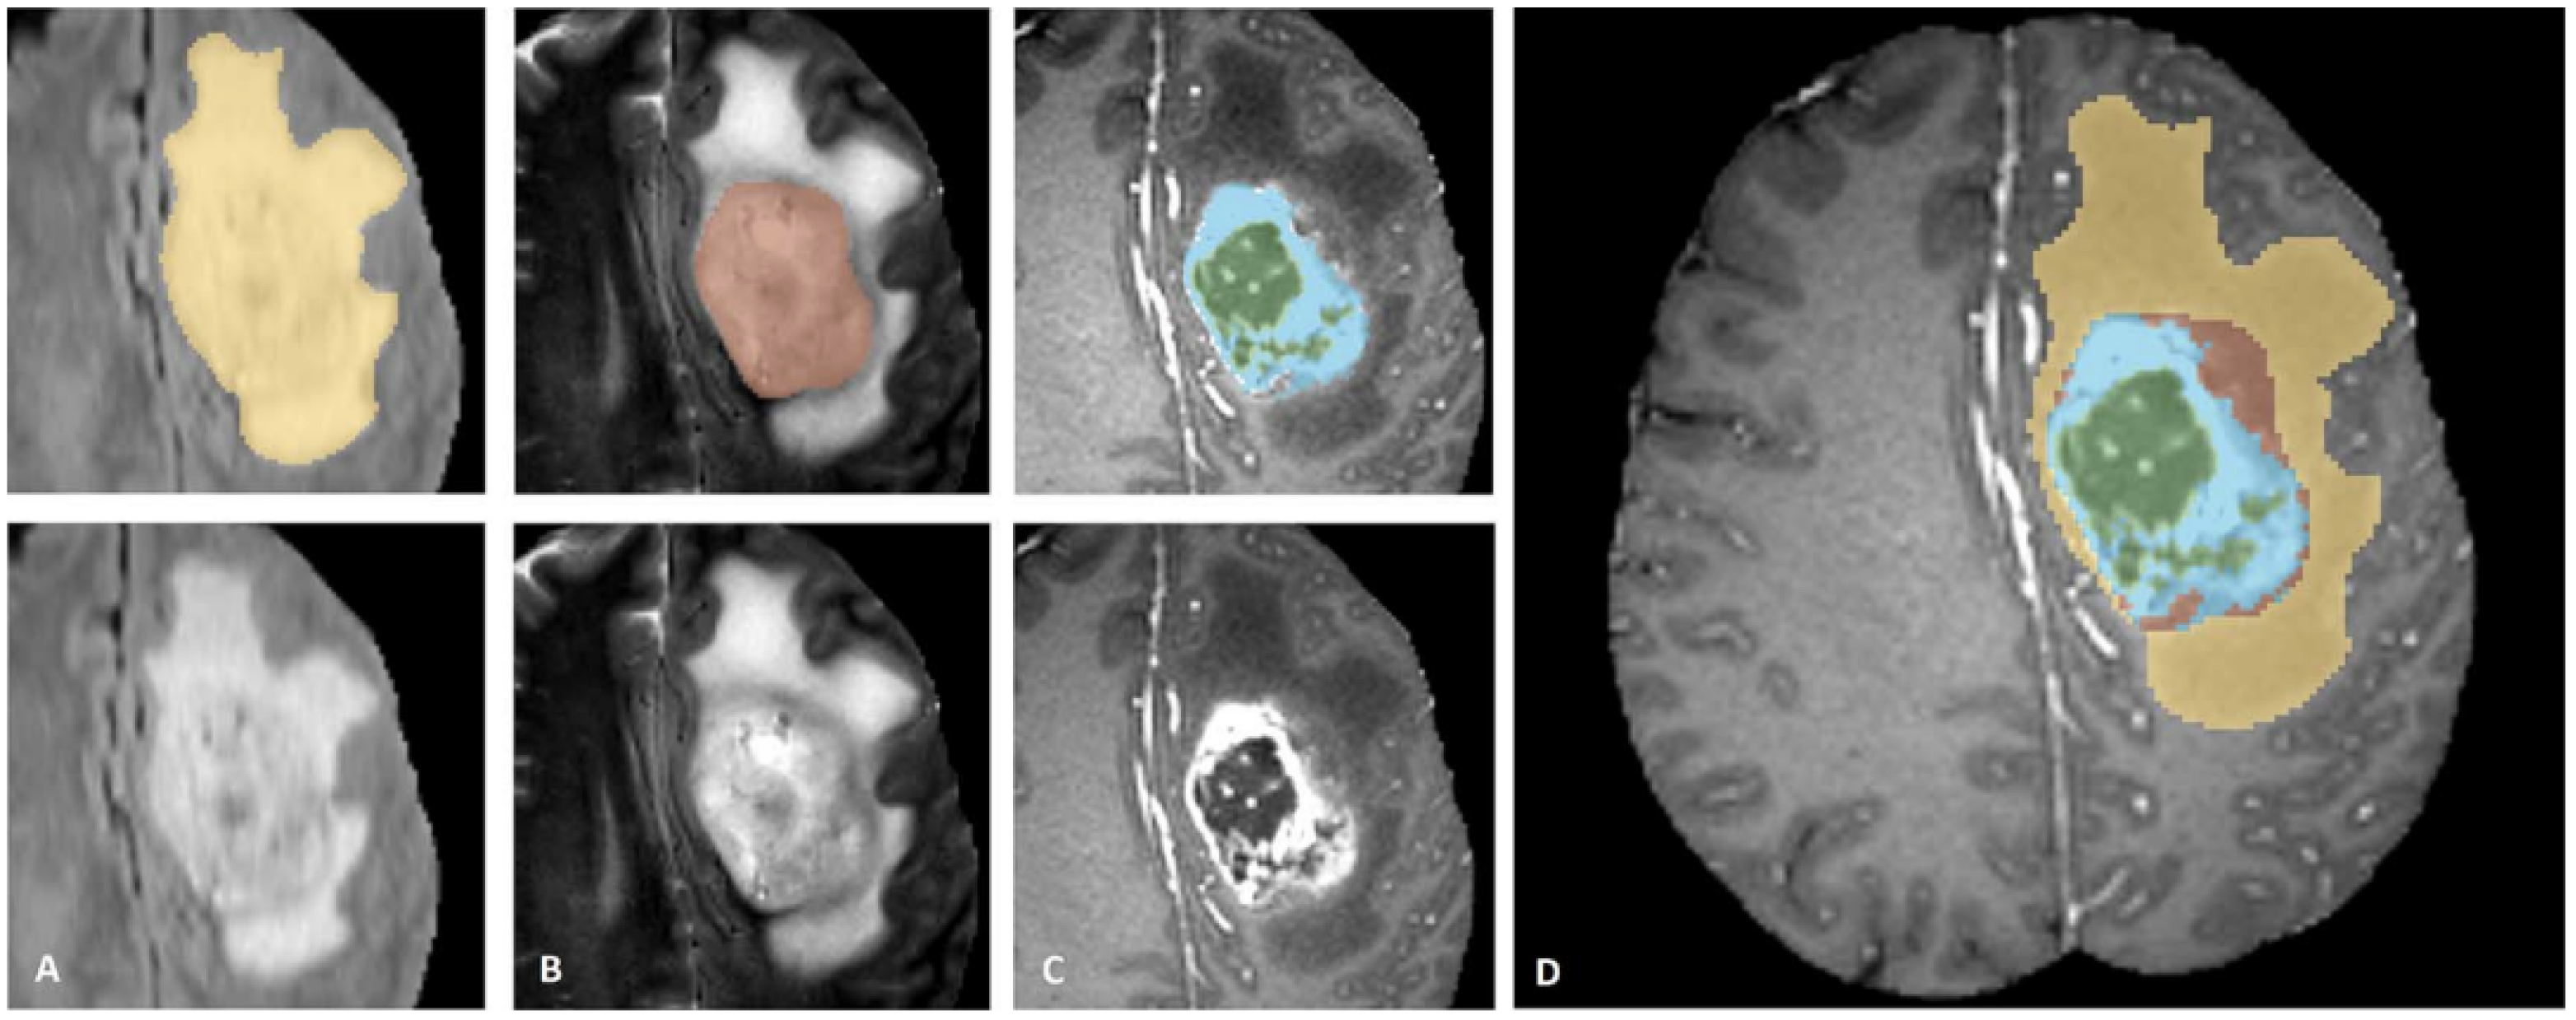

3.3. Segmentation

3.4. Tumor Shape Radiomics Features Analysis

4.1. Segmentation